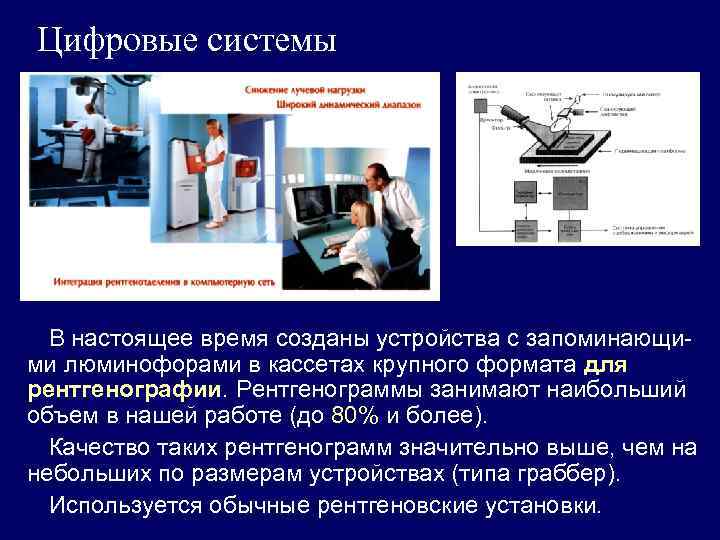

Цифровые системы В настоящее время созданы устройства с запоминающими люминофорами в кассетах крупного формата для рентгенографии. Рентгенограммы занимают наибольший объем в нашей работе (до 80% и более). Качество таких рентгенограмм значительно выше, чем на небольших по размерам устройствах (типа граббер). Используется обычные рентгеновские установки.